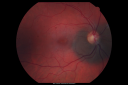

Melanoma1498 views40 Year old male

Choroidal Melanoma1482 views

Melanoma1457 viewsYoung male with large Melanoma